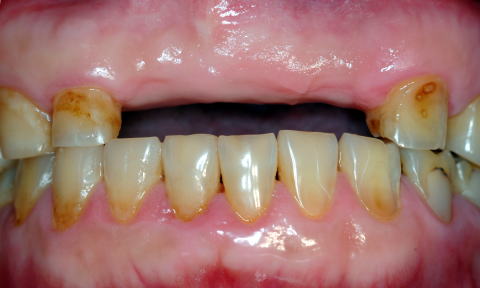

■症例1−1 酸蝕症 Acid Erosion(酢・ポン酢・ビール・焼酎)

全顎に渡り、唇側は酸蝕のためEnamel質が薄くなり、歯頸部付近では象牙質まで露出。Plaque Controlが悪いため、特徴的な歯頸部に表在性のう蝕と着色が診られる。咬合高径が小さいため、義歯の設計が極めて困難である。当然Under

Cutもほとんどなくなっている

患者:69歳、男性

高血圧にてコニール服用中(130/80mmHg)。HEAVY DRINKER(毎日ビール2〜3本、焼酎)。GOT(58IU/l),γ−GTP(174IU/l),高尿酸値(7.3m/dl)。高血圧予防として禁酒は出来ないため、減塩目的で長年醤油の代わりにポン酢や酢を多用していた。その結果、重度酸蝕症に罹患。さらにビール(pH4)と焼酎(pH5)が拍車をかけた。成人男性にしては極めて小さい歯牙形態に陥ってしまった。